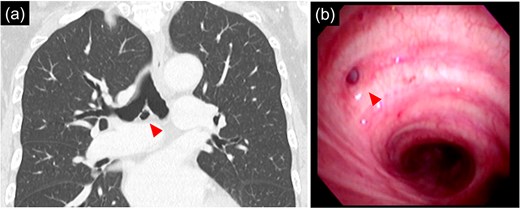

(a) 9 mm size bronchial diverticulum located at the subcarinal region. (b) Bronchial diverticulum opening in the right main bronchus and two rings distal to the carina.

Bronchoscopy after intubation revealed an orifice of the BD in the cartilage of the right main bronchus with two rings below the carina (Fig. 2). First, a lower mediastinal lymph node dissection and BD were performed. The area around the BD was prone to bleeding and the lymph nodes were in close contact with each other (Fig. 3), making it difficult to separate them from the BD. After identifying and exposing the stalk of a BD, ligation of the diverticulum with ENDOLOOP® PDS II Ligature allowed for control of bleeding and the lymph nodes could be safely removed from the BD (Video 1).